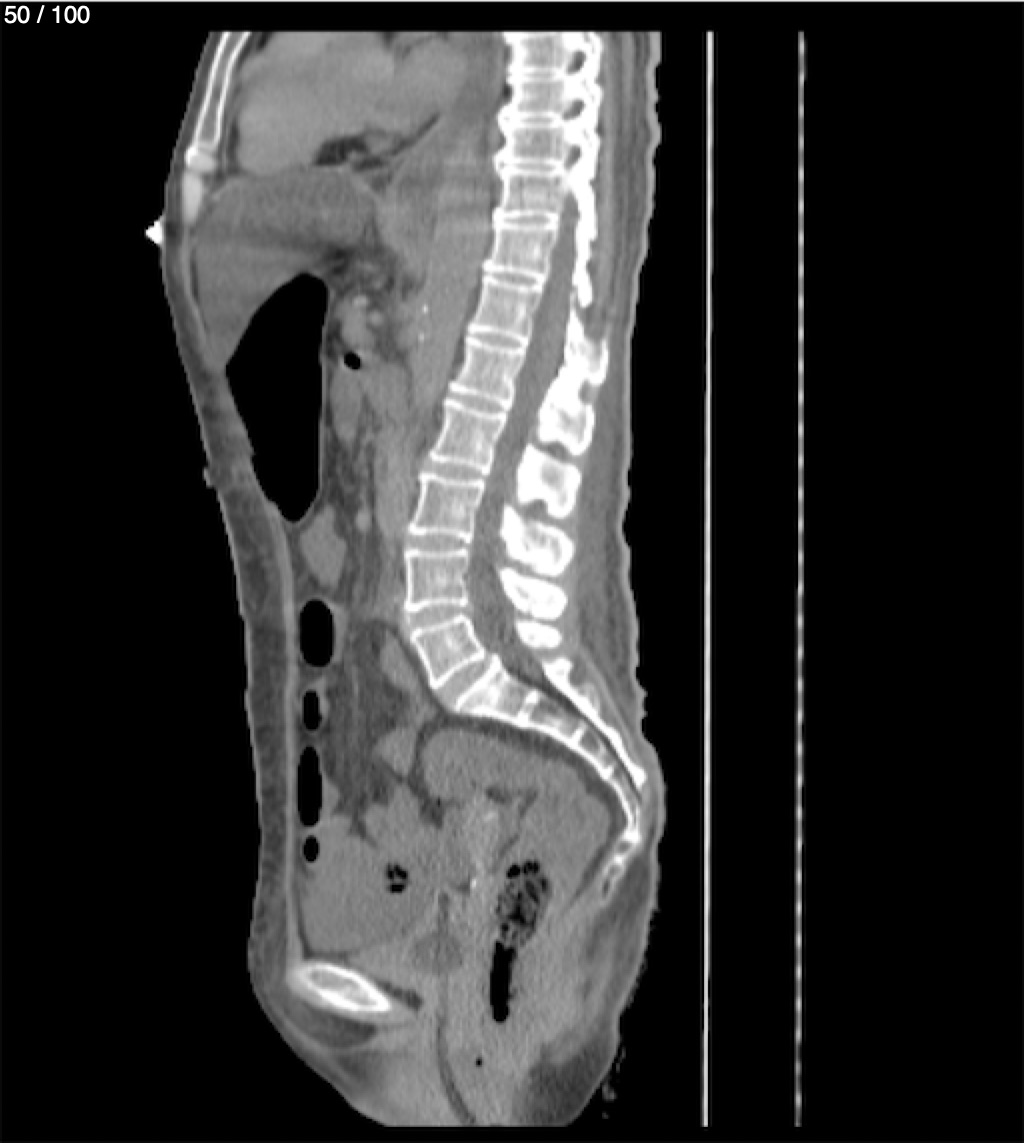

Hilda Geronimo Mendez 60A - T.C Abdomen Simple